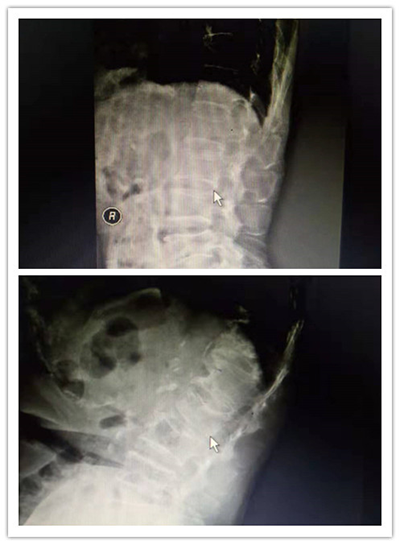

术中、术后影像

术后患者疼痛消失,即刻下地活动。